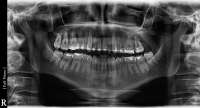

Сегодня делал обий снимок. Хуй знает, как его описать, мне выдали диск с ним, там такая хуйня, что доктор может колесиком водить-приближать-отдалять и снимок меняется, как будто 3D или хуй пойми. Мне не во что диск вставить, лол, не могу посмотреть, что там. Доктор нашла 3(!) кариеса, 1 сверху справа, второй сверху слева и третий на соседнем зубе начинающий. Причем на том зубе, который я полгода назад восстановил-нарастил. С восьмерками пока что нихуя не делать сказала, но чую, что потом они вылезут криво. Она сказала, что они будут выходить "повернутыми". Пока что еще внутри десен они(верхние).

Самая жопа в том, что под нижней 6кой, под самым корнем у меня образовалась киста(если не путаю). Док показала на компе большую черную точку. Сам зуб с удаленными каналами 12 лет назад, сказала, что залупа тебе. Или удалять или находить какого-то стоматолого с микроскопом, разбирать зуб и пытаться чистить. Пиздец, блядь.

Вчера делал панорамный снимок. Всё как >>513480 сказал, ортодонт взял его только посмотреть. Внимание, вопрос знатокам, ортодонт посмотрел на второй пикрелейтед и сказал, что зуб в котором штифт нужно переделывать - канал не полностью залечили, а так же второй зуб - там тоже проблема с каналом и что если ставить брекеты, то им обоим придет пизда. Когда это лечить не понятно, времени в обрез, завтра пойду к своему врачу который год-полтора назад мне эти зубы лечил, послушаю что скажет. В то, что она плохо сделала не хочется верить, но нужно быть реалистом.

Да, надо перелечивать тот что левый (без штифта). Там Уже процесс в области верхушки корня есть как мне кажется, а то что я прав 99.9999% , а тот что со штифтом надо вообще посмотреть на прицельном снимке. Мне он не очень нравится.